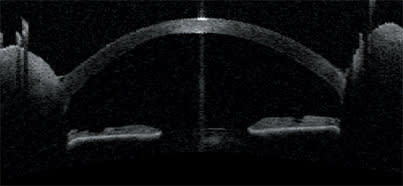

The Visante OCT also is proving to be useful in association with intracorneal refractive implants. The OCT images on this page depict an ultra-thin intracorneal implant currently being evaluated in patients for the correction of presbyopia (AcuFocus Inc.). Based on small-aperture optics, an optimized pinhole, the implant is 3.80 mm in diameter and has a 1.60-mm aperture.

The Visante OCT's high-resolution corneal scan and anterior-segment scan pinpoint the location of the implant and allow measurement of its diameter and thickness.

The Visante OCT shows the flap made for implantation of the intracorneal refractive implant. The surgeon can visualize the implant's edge and the light coming through its fenestrations.

The anterior-segment profile includes the iris and the angle for precise location of the intracorneal implant.